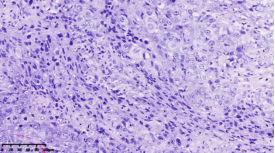

在本项研究中����,研究人员利用基本的组织形态学方法及免疫组织化学法对TNBC进行分型��:腔面雄激素受体型(LAR)(图1A)��,免疫调节型(IM)(图1B)�����,基底样免疫抑制型(BLIS)(图1C)���,间充质型(MES)(图1D)�����。评价各亚型临床病理参数(如发病年龄��、肿物大小���、淋巴结转移等)���,组织形态学(肿物中央瘢痕形成���、浸润模式����、肿瘤间质浸润淋巴细胞���、细胞排列方式���、细胞核形态��、核分裂计数���、间叶化生等)以及免疫表型(p53����、Rb���、PD-L1���、MMR等)�����,结果显示���:1.TNBC分型的临床病理����、组织形态学和免疫表型特征不尽相同���,有望成为复杂的基因表达谱分析的替代选择����,为TNBC的分型治疗及靶向治疗提供理论依据��;2.生物标记物 PD-L1作为重要的生物学指标�����,对个体化治疗及免疫治疗有重要的临床指导价值��;3.乳腺癌中dMMR作为一个低频发生事件��,不太可能作为免疫治疗有效性的评估手段����。该成果发表在Virchows Archiv期刊����,题目为“Subclassifying Triple-Negative Breast Cancers and Its Potential Clinical Utility”��。文章DOI为����:10.1007/s00428-022-03329-0�����。

图1. 基于组织形态学及免疫组织化学标记物的TNBC分型